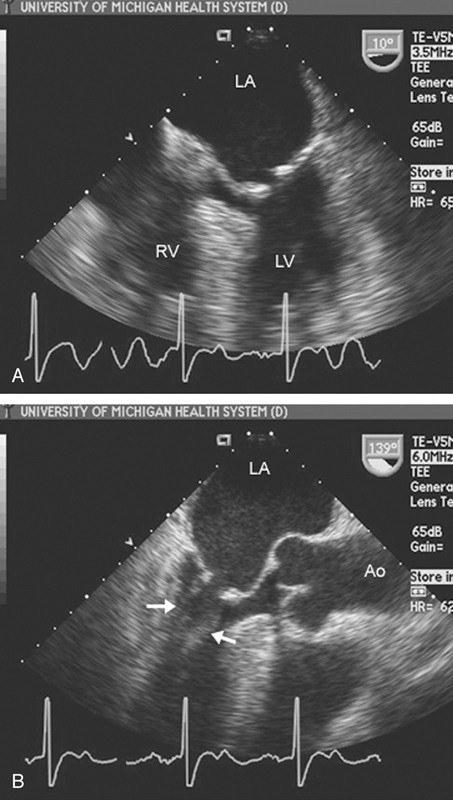

فحوصات تشخيصية لبعض امراض القلب والشرايين التاجية